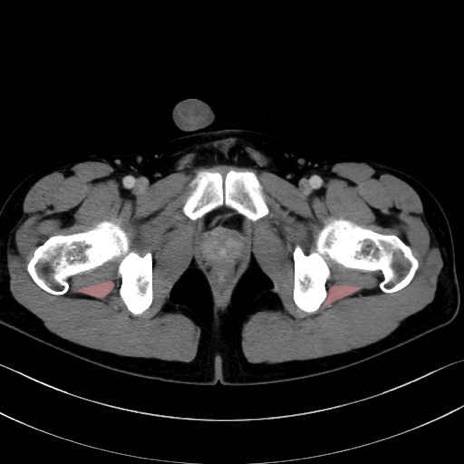

大腿方形筋(Quadratus femoris muscle)のCT画像の解剖

4. 深層外旋六筋(股関節の深部)

大腿方形筋 (Quadratus femoris)